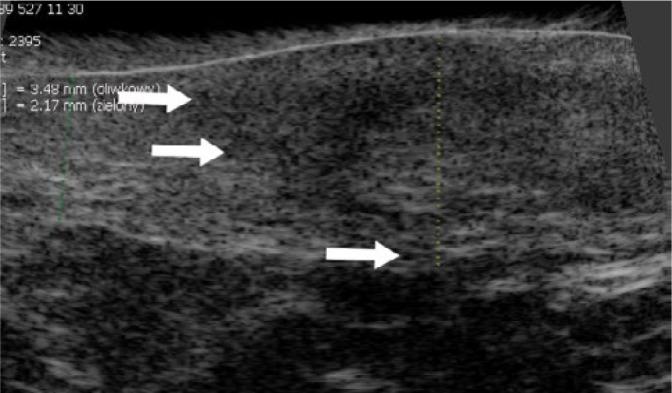

Paget's disease of the vulva is a rare skin cancer accounting for less than 1% of all vulvar neoplasias. Surgery is the first treatment of choice. Unfortunately, it is insufficient in many cases, which require further treatment, and the risk of recurrence is high. We present a case of an 85-year-old woman who underwent surgery due to Paget's disease of the vulva. A preoperative skin imaging using a high-frequency 48 MHz mechanical probe was used to assess the lesion margins. Typical high-frequency ultrasonographic features of vulvar Paget's disease were identified and analyzed. This is the first report of high-frequency ultrasonography imaging of vulvar Paget's disease.

外阴佩吉特病是一种罕见的皮肤癌,占所有外阴肿瘤的比例不到1%。手术是首选的治疗方法。不幸的是,在许多情况下手术并不充分,需要进一步治疗,且复发风险很高。我们报告一例85岁因外阴佩吉特病接受手术的女性病例。术前使用高频48MHz机械探头进行皮肤成像以评估病变边缘。识别并分析了外阴佩吉特病典型的高频超声特征。这是外阴佩吉特病高频超声成像的首例报告。